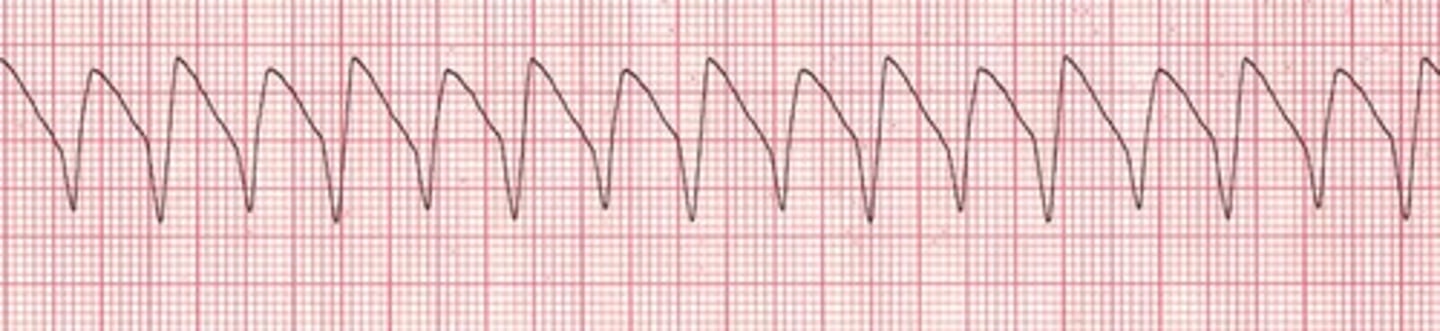

What is v fib?

you are dead, ventricles are quivering, clients have no pulse/BP/RR. fatal if not terminated in 3-5 minutes. Want Coarse v fib rather than fine because there is more of a rhythm to shock.

What is the treatment for v fib?

defibrillation immediately, CPR, epinephrine/vasopressin, O2, Amiodarone (V-FIB = D-FIB)